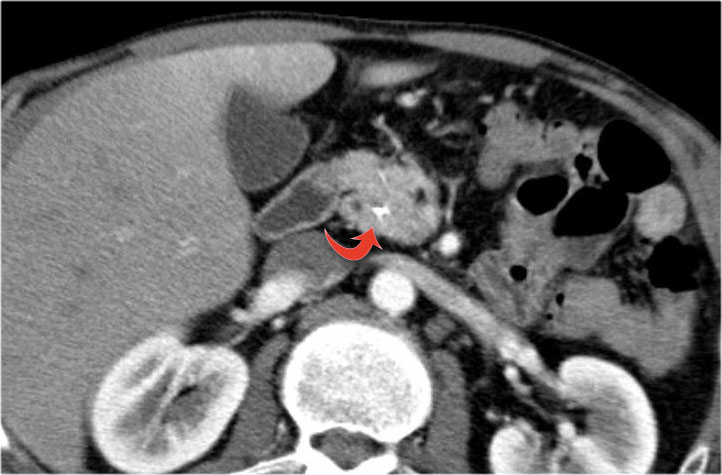

Bệnh nhân này bị viêm tụy mạn tính.

Lưu ý các vôi hóa ở đầu tụy (mũi tên cong).

Có nhiều nang giả tụy lan dài vào tận trung thất, gây chèn ép tim (mũi tên đỏ).